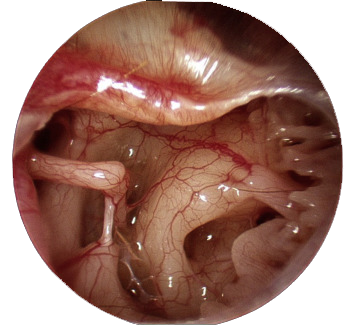

♦ Middle ear Endoscopy (મિડલ ઇયર એન્ડોસ્કોપી)

- આમાં મિડલ ઈયર ને એન્ડોસ્કોપ નો ઉપયોગ કરી એક્ઝામિનેશન કરવામાં આવે છે કે જેમાં કોઈ પણ એક્યુટ અથવા ક્રોનિક મિડલ ઈયર નું ઇન્ફેક્શન છે કે નહીં તે જોવા માટે અથવા કોઈપણ એબનોર્માલિટી છે કે નહીં તે જોવા માટે કરવામાં આવે છે.